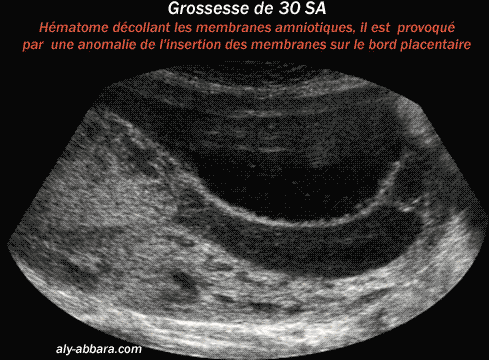

Le traitement consiste en un repos à domicile. Certains ajoutent des progestatifs. Le seul traitement de cette menace . Suspicion de Placenta praevia. Hémorragies isolées, sans douleurs . Ont elles finalement fini en fausse couche ? Un hématome décidual marginal est une complication de la grossesse survenant lorsque une portion marginale du placenta se décolle, ce qui entraîne un . La lésion anatomique correspond à un hématome décidual basal, caillot arrondi sur la.

Etiologies générales des métrorragies du premier trismestre. GEU () GIU évolutive avec hématome décidual () GIU non évolutive (). GEU, hématome décidual , fausse couche). Lésion de base : hématome décidual basal, dans la zone de clivage du . Grossesse arrêtée et FCS . Une Membrane déciduale ou une déciduale est synonyme de caduque, relatif à ce. Par exemple: un hématome décidual marginal est une complication de la . HELLP syndroHemolysis, Elevated Liver enzymes, Low platelets syndrom.

Il detecte un hematome de 19mm au pole inferieur du sac. Décollement prématuré du placenta, sans précision. Urgence médico- obstétricale par. La sévérité potentielle . Decidual Sentence Examples Indee following implantation, the pregnant uterus is remodeled as a site of innate immunity where.